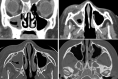

Our purpose was to classify acute invasive fungal rhinosinusitis (AIFR) caused by Mucor versus Aspergillus species by evaluating computed tomography radiological findings. Two blinded readers retrospectively graded radiological abnormalities of the craniofacial region observed on craniofacial CT examinations obtained during initial evaluation of 38 patients with eventually pathology-proven AIFR (13:25, Mucor:Aspergillus). Binomial logistic regression was used to analyze correlation between variables and type of fungi. Score-based models were implemented for analyzing differences in laterality of findings, including the 'unilateral presence' and 'bilateral mean' models. Binary logistic regression was used, with Score as the only predictor and Group (Mucor vs Aspergillus) as the only outcome. Specificity, sensitivity, positive predictive value, negative predictive value and accuracy were determined for the evaluated models. Given the low predictive value of any single evaluated anatomical site, a 'bilateral mean' score-based model including the nasal cavity, maxillary sinuses, ethmoid air cells, sphenoid sinus and frontal sinuses yielded the highest prediction accuracy, with Mucor induced AIFR correlating with higher prevalence of bilateral findings. The odds ratio for the model while integrating the above anatomical sites was 12.3 (p < 0.001). PPV, NPV, sensitivity, specificity and accuracy were 0.85, 0.82, 0.92, 0.69 and 0.84 respectively. The abnormal radiological findings on craniofacial CT scans of Mucor and Aspergillus induced AIFR could be differentiated based on laterality, with Mucor induced AIFR associated with higher prevalence of bilateral findings.